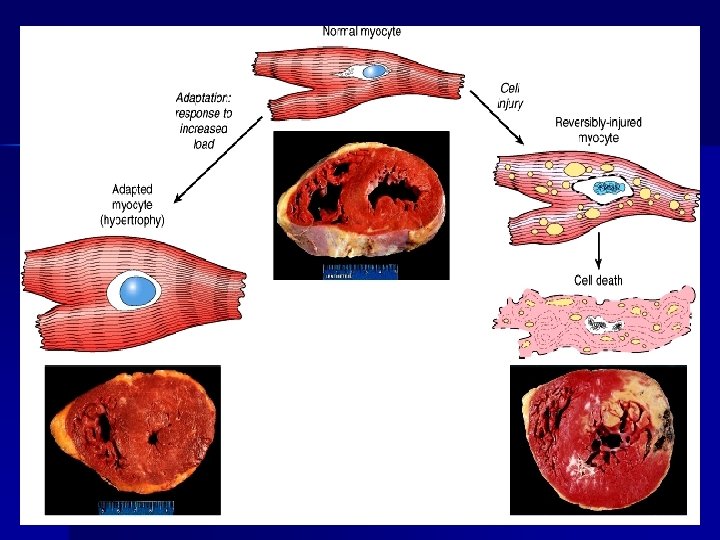

ADAPTACIÓN CELULAR ESTRESS Demanda funcional aumentada Lesión Celular reversible Estrés persistente ADAPTACIÓN Hipertrofía Hiperplasia Atrofía Metaplasia Displasia? Leve Grave Lesión celular irreversible Almacenamiento Desaparición del estrés Célula normal Necrosis por coagulación

HIPERTROFIA - Aumento del tamaño de un órgano o tejido por aumento del tamaño celular y aumento de su función. - Aumento de componentes celulares y estructurales. - El Útero es receptor estrogénico en el músculo liso: proteína y ADN: hipertrofia fisiológica. - Músculo estriado y cardiaco: mayor capacidad de hipertrofia. - Aumento de síntesis de proteínas y miofilamentos.

- Demanda funcional aumentada. Músculos, hipertrofía cardiaca por hipertensión, hepatocitos (aumento de REL por estímulo de fenobarbital y drogas hipolipemiantes)- hepatomegalia fisiológica - Hipertrofia del riñón contralateral. - Más frecuentes en tejidos pemanentes y estables.

Patogénesis de la hipertrofia n Un estímulo induce a la activación de los protooncogenes, lo que da lugar al aumento de factores de transcripción en la síntesis de ARN y ADN (que es la causa de la poliploidía nuclear)